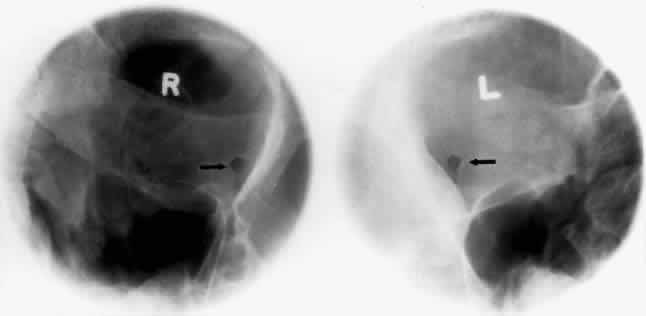

BASAL PROJECTION (SUBMENTO-VERTEX)

The basal projection (Fig. 5) for the evaluation of the sphenoid sinus and skull base was described initially by Arthur Schuller12 in 1905 and later popularized in this country by Bowen.13 This projection is obtained with the patient's neck extended either in the supine or upright position. The top of the head is placed so that the infraorbitomeatal line is parallel with the x-ray cassette. The x-ray beam is directed at right angles to the infraorbitomeatal line.5,6 This view shows the lateral walls of the orbit and maxillary sinuses well. The nasopharynx, pterygoid plates, pterygopalatine fossa, and the sphenoid and ethmoid sinuses may also be inspected. Because of the extreme head position, any history of a neck injury is a contraindication to this radiologic study.

Fig. 5. A. Schematic showing positioning for a basal projection. (CR, central ray; IM, infraorbitomeatal line) B. Radiograph of a basal projection. (a, zygomatic arch; b, orbit; c, lateral orbital wall; d, posterior wall of maxillary sinus; e, pterygoid plate; f, sphenoid sinus) (A; Rao VM, Gonzalez CF: Plain film radiography and polytomography of the orbit. In Gonzalez CF, Becker MH, Flanagan JC [eds]: Diagnostic Imaging in Ophthalmology, pp 1–7. New York, Springer Verlag, 1986)